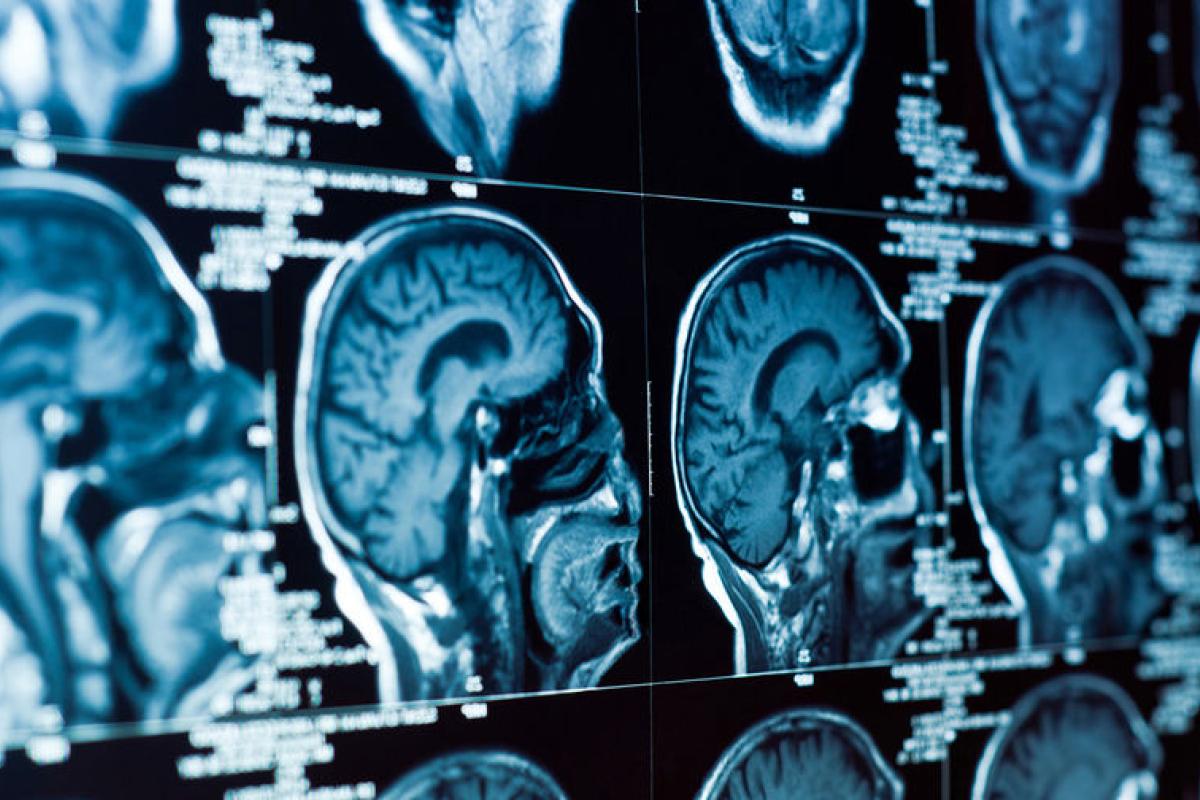

Недавно нидерландские медики обнаружили в голове человека новый орган, передает Час Пик со ссылкой на украинские СМИ.

В задней части носоглотки были обнаружены трубчатые железы, о которых ранее наука и не подозревала.

Исследователи полагают, что это четвертый набор основных слюнных желез, расположенных за носом и над небом, недалеко от центра головы человека, который представлен в виде двусторонней структуры.